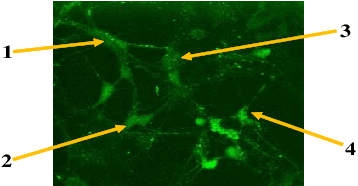

Abstract:Quantification of information content and its temporal variation in intracellular calcium spike trains in neurons helps one understand functions such as memory, learning, and cognition. Such quantification could also reveal pathological signaling perturbation that potentially leads to devastating neurodegenerative conditions including Parkinson's, Alzheimer's, and Huntington's diseases. Accordingly, estimation of entropy rate, an information-theoretic measure of information content, assumes primary significance. However, such estimation in the present context is challenging because, while entropy rate is traditionally defined asymptotically for long blocks under the assumption of stationarity, neurons are known to encode information in short intervals and the associated spike trains often exhibit nonstationarity. Against this backdrop, we propose an entropy rate estimator based on empirical probabilities that operates within windows, short enough to ensure approximate stationarity. Specifically, our estimator, parameterized by the length of encoding contexts, attempts to model the underlying memory structures in neuronal spike trains. In an example Markov process, we compared the performance of the proposed method with that of versions of the Lempel-Ziv algorithm as well as with that of a certain stationary distribution method and found the former to exhibit higher accuracy levels and faster convergence. Also, in experimentally recorded calcium responses of four hippocampal neurons, the proposed method showed faster convergence. Significantly, our technique detected structural heterogeneity in the underlying process memory in the responses of the aforementioned neurons. We believe that the proposed method facilitates large-scale studies of such heterogeneity, which could in turn identify signatures of various diseases in terms of entropy rate estimates.